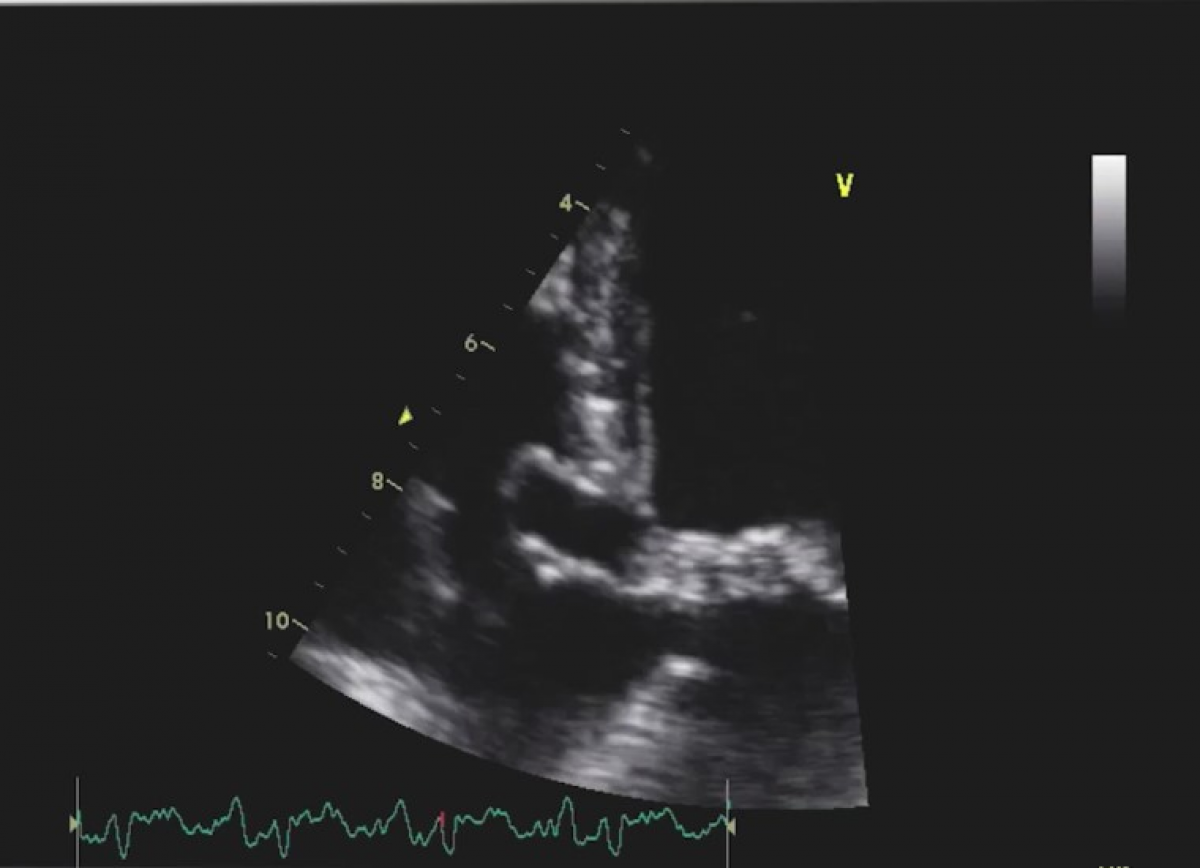

Pacjentka z zawałem bez uniesienia odcinka ST.

Powikłania zawału serca (wtórna niedomykalność mitralna, tamponada, krwiak osierdzia, tętniak rzekomy).

Echokardiografia przezklatkowa.

Diagnostyka powikłań mechanicznych zawału mięśnia sercowego.